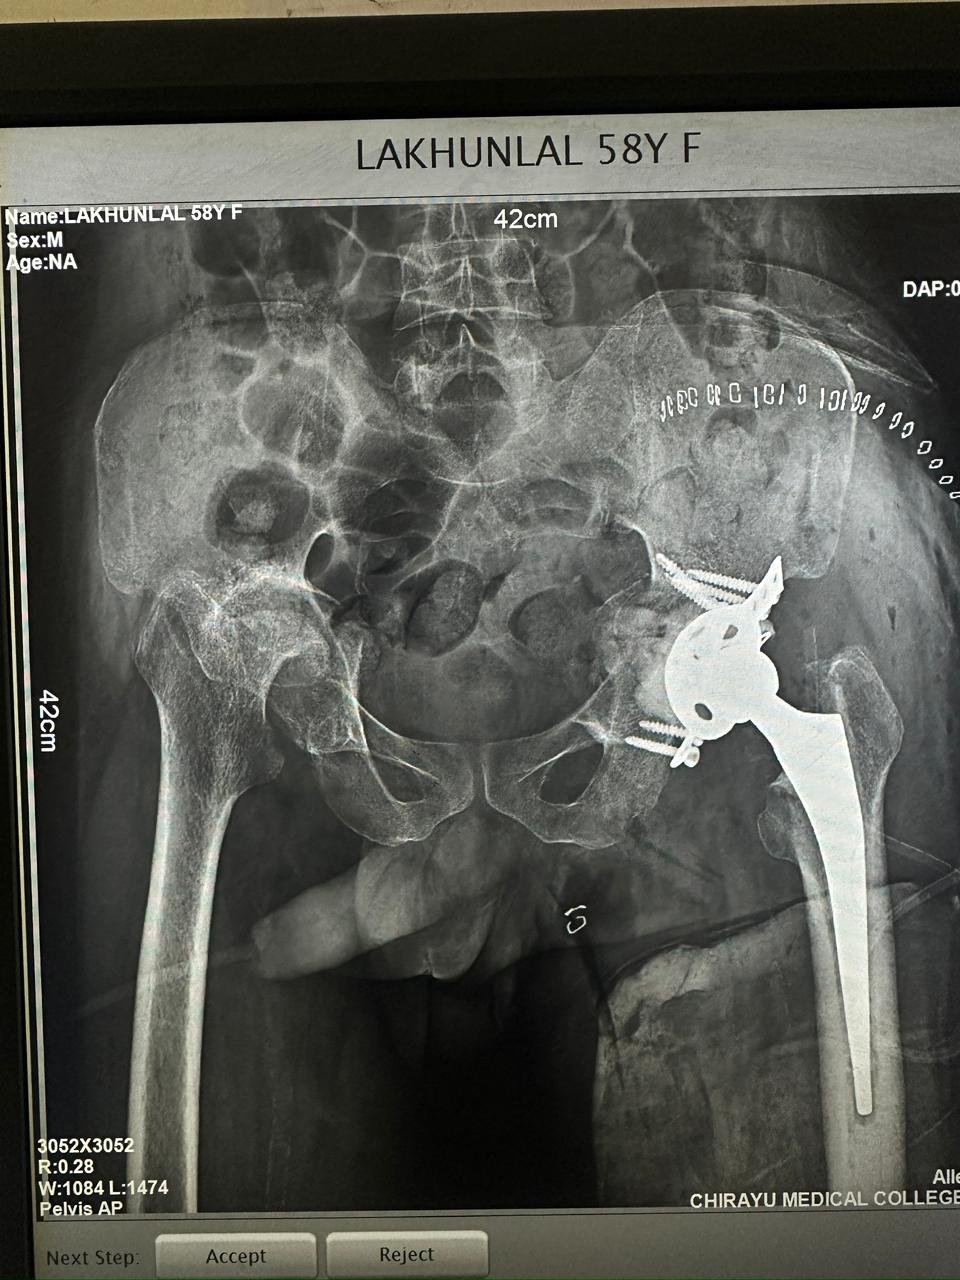

Orthopaedic Surgeon | Arthroscopy & Joint Replacement Specialist

Dr. Aditya Tripathi is a dedicated and skilled Orthopaedic Surgeon specializing in sports injuries, arthroscopy, and joint care. Known for his clinical precision, ethical practice, and patient-first approach, he focuses on helping patients regain mobility, strength, and confidence through evidence-based orthopaedic treatment. His academic background and hands-on clinical training reflect a strong foundation and a commitment to excellence in orthopaedic care.

| 2022-2023 | Former Fellow in Robotic joint replacement department | Lokmanya hospital,Pune(Mentor Dr Narendra Vaidya) |

Specialization And Expertise

- Hip Replacement Surgery